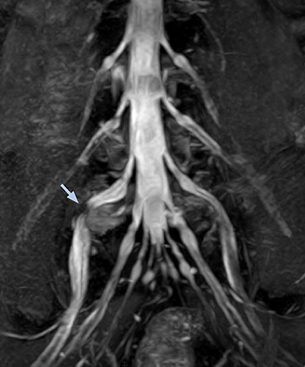

According to Tanji, methods such as ProSet FFE, STIR or 3D VISTA are anatomically nonselective because background signals, for instance from blood vessels, often interfere with nerves, which hampers evaluation of details, especially at the peripheral side of the nerves.

“The intra-luminal signal of veins, especially around the intervertebral space, can be suppressed well with NerveVIEW. As a result, we can easily observe the detailed nerve structure around the posterior ganglion,” he says. “This is why we use 3D NerveVIEW for intraforaminal stenosis and extraforaminal stenosis/herniation (lateral disc herniation). On the other hand, if herniation is suspected to exist inside the dorsal root ganglion (DRG), balanced TFE or ProSet-FFE is applied. NerveVIEW is not suitable for evaluating the median type of herniation.”

The SE-EPI DWI-based method for MR neurography works well for large FOV exams like whole-body MRI, but focal examination of nerves is often limited by the attainable spatial resolution (both inplane and slice direction) and geometric distortion. “3D NerveVIEW achieves higher in-plane resolution – close to our other routine spine sequences – and the source images can be used instead of adding a fat-suppressed T2-weighted sequence,” Tanji says.

“For both brachial and lumbar plexus, we are currently using a 230 mm FOV and voxels of about 1 x 1 x 2 mm acquired (1 x 1 x 1 mm reconstructed). This provides us a good representation of the nerves, even though this FOV is relatively small. Regarding the inplane resolution, we hope to be able to bring that down to 0.7 mm, similar to our typical 2D multislice T2W images,” says Tanji.

“Recently, the two surgical methods extreme and oblique lateral interbody fusion (XLIF and OLIF) have become mainstream for minimally invasive treatment of lumbar spinal canal stenosis and intervertebral foramen stenosis. With these surgical techniques, the spine is approached from the flank, and prior knowledge of the exact anatomy of the lumbosacral plexus would be extremely helpful. To that end, high slice resolution (less than 1 mm acquisition) that enables sharper sagittal MPR images will be needed.”